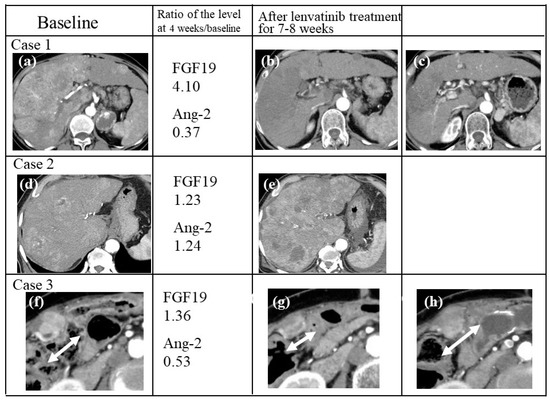

2.10. Case Presentations